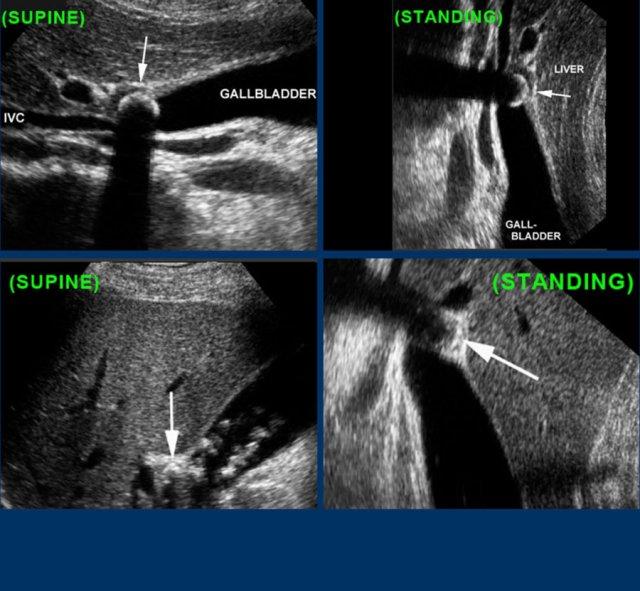

Ở tư thế nằm ngửa, một viên sỏi (mũi tên) được phát hiện tại cổ túi mật.

Sau khi đứng dậy, cúi người và đi lại, viên sỏi (mũi tên) không di chuyển xuống, do đó phải là sỏi kẹt.

Sỏi trong ống túi mật đôi khi không thể hiển thị được trên mặt phẳng siêu âm theo trục dọc của túi mật.

Hình ảnh của một bệnh nhân bị phình to túi mật cấp tính do sỏi kẹt.

Sỏi kẹt không thể hiển thị được trên trục dọc của túi mật, do vị trí nằm ở phía trong của ống túi mật (mũi tên).